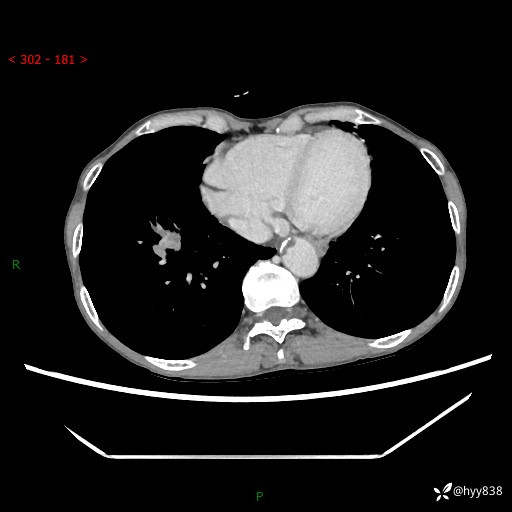

69岁/女,发现肺占位3天余。精彩好病例,请慧诊---(有结果)

【患者信息】:69岁/女

【主诉】:发现肺占位3天余

【现病史及既往史】:患者3天余前因既往肺气肿复查胸部CT发现“右肺下叶结节、双肺多发结节、双肺门及纵膈淋巴结增大”,平素偶有咳白色粘液痰,下肢乏力,无明显低热、盗汗、咯血、胸痛、喘气等不适,今为求明显结节性质遂来我院门诊就诊,门诊以“孤立性肺结节”收治入院。 起病以来,患者精神饮食睡眠一般,大小便正常,体力无明细变化,体重近年来较前下降。

【检查】:胸部CT增强